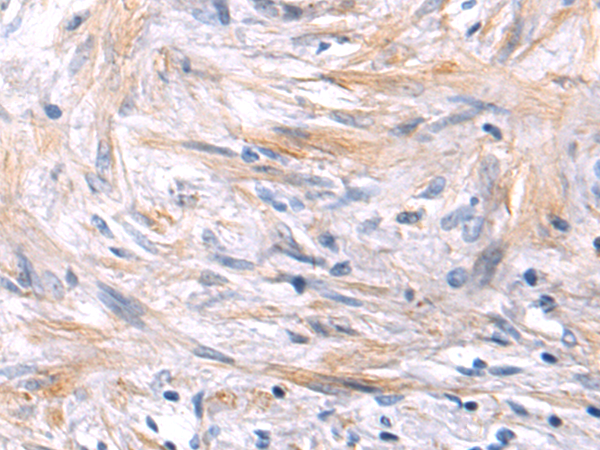

分类: 科研抗体货号: P10832别名: ALK-SMase应用: IHC反应种属: Human, Rat